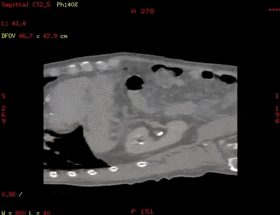

Smart D4D:腹部4D成像

在放射治疗科,我可以进行放疗患者CT定位扫描,我可以不依靠第三方厂家,自己做四维呼吸门控扫描,我可以自动去除患者金属伪影,我的老搭档SIM兄弟可以自动勾画正常器官外轮廓,支持在四维CT图像上实时定义修改结构,可以存储为RT DICOM格式发送给TPS。